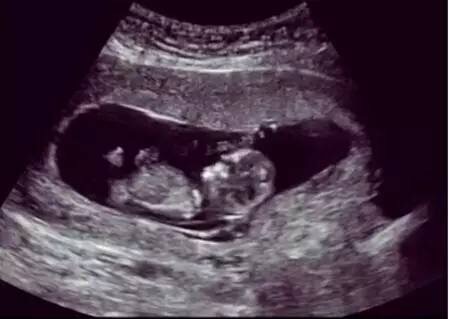

超声波使用的是一种声波,不是离子射线。目前为止,从没有过诊断性超声波造成胎儿损伤的报道出现,包括多普勒彩超。孕期超声波是不受威胁的,这也是为什么现代妇产科产检不用x线,而常规用超声波。

核磁共振同样不使用离子射线,而是使用磁场改变体内的氢离子能量状态而成像。所以是不会对胎儿造成损害的。所以当需要检查胎儿中央神经系统发育情况或者确诊胎盘前置等胎盘异常时,核磁共振是权威选择。